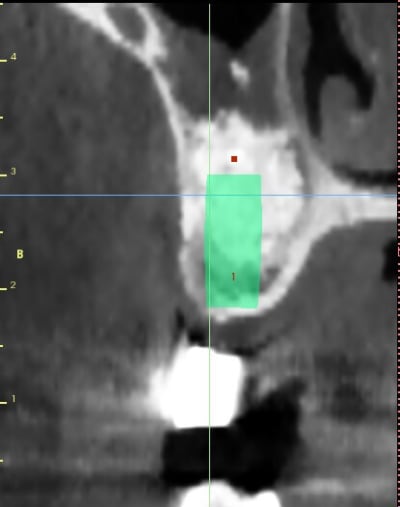

patiente ayant été implantée il y a 12 jours et toujours mal

le sinus lift a été pratiqué il y a 8 mois

Aspect lacunaire du biomat au scanner = sucre mouillé infecté...car non vivant et non vascularisé

bon je m'en doutais un peu que ça venait des lacunes dans le bio oss

Toujours est il qu'avec un agrandissement on verrait sûrement plein de petites lacunes , mais déjà là les grosses...